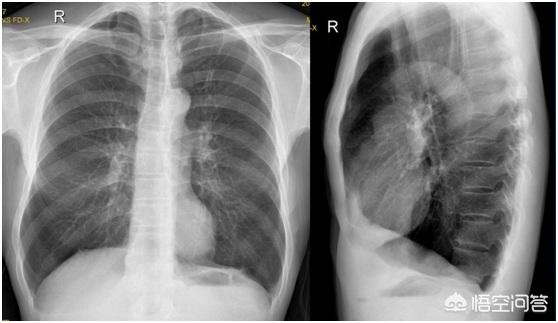

多くの高齢の喫煙者は、胸部X線検査で、医師は、これは肺気腫ですああと言うでしょう。胸部フィルムで肺が2つ見えるのは、確かに肺気腫の徴候であり、胸部全体が膨張し、バケツのようになっているので、バケツ胸と呼ばれています。私たち医師は、患者の胸の膨らみと喫煙歴を見れば、すぐにこの人は肺気腫かもしれないとわかる。

X線所見:①胸腔の前後径が樽型に拡大し、肋間が広がる。両側の横隔膜上部の位置が低下し、横隔膜上部が平坦になる。肺の透光性は増加し、肺の質感は薄く、細長く、直線的になる。透視下では、両横隔膜の運動が弱くなる。縦隔、心膜、皮下組織に間質性肺気腫を生じることが多い。(6)肺胞破裂では、閉鎖性気胸や肺無気肺を生じることがある。